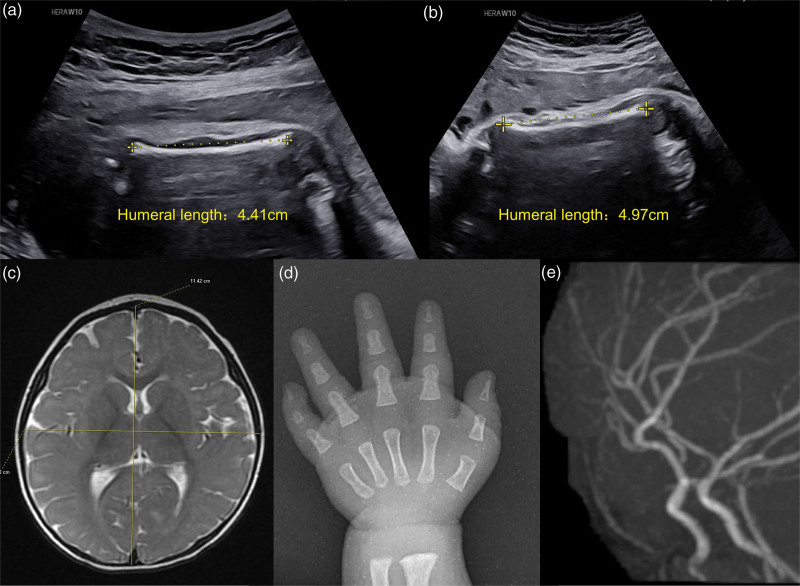

Dual diagnosis of microcephalic osteosplastic primary dwarfism type II and benign familial infantile seizure type 2: a case report.